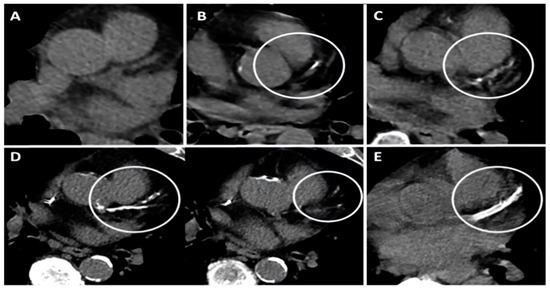

| Thorax CT-CACS | 3.5 (1–6.7) | 0 (0–3) | <0.001 |

| Thorax CT-CACS +, n (%) | 84 (%81) | 100 (%45) | <0.001 |

| Thorax CT CAC + aortic calcification + | 5.28 | 3.13–8.91 | <0.001 | 3.85 | 1.69–8.78 | 0.001 |

| C | CACS + Aort calcification + | 1 point |